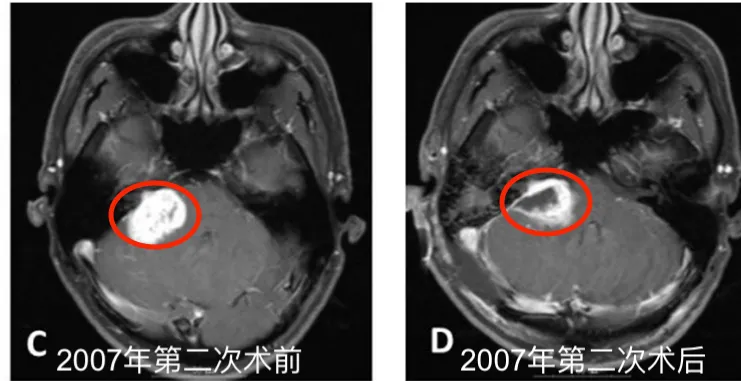

2005年8月,为控制残余肿瘤的继续生长,患者接受了伽玛刀放射外科治疗,边缘照射剂量为10Gy(50%等剂量线)。这一方案在当时属于国际上通行的处理策略,对于残留或复发的小型听神经瘤,放射外科治疗被普遍认为是低风险、高效的控制手段。

然而,2007年5月,影像学检查提示残留病灶出现进展,患者随即接受第二次手术切除。术中发现肿瘤与面神经、听神经以及后组颅神经存在严重粘连,蛛网膜间隙消失,最终仍只能完成次全切除。术后病理依然报告为良性前庭神经鞘瘤。